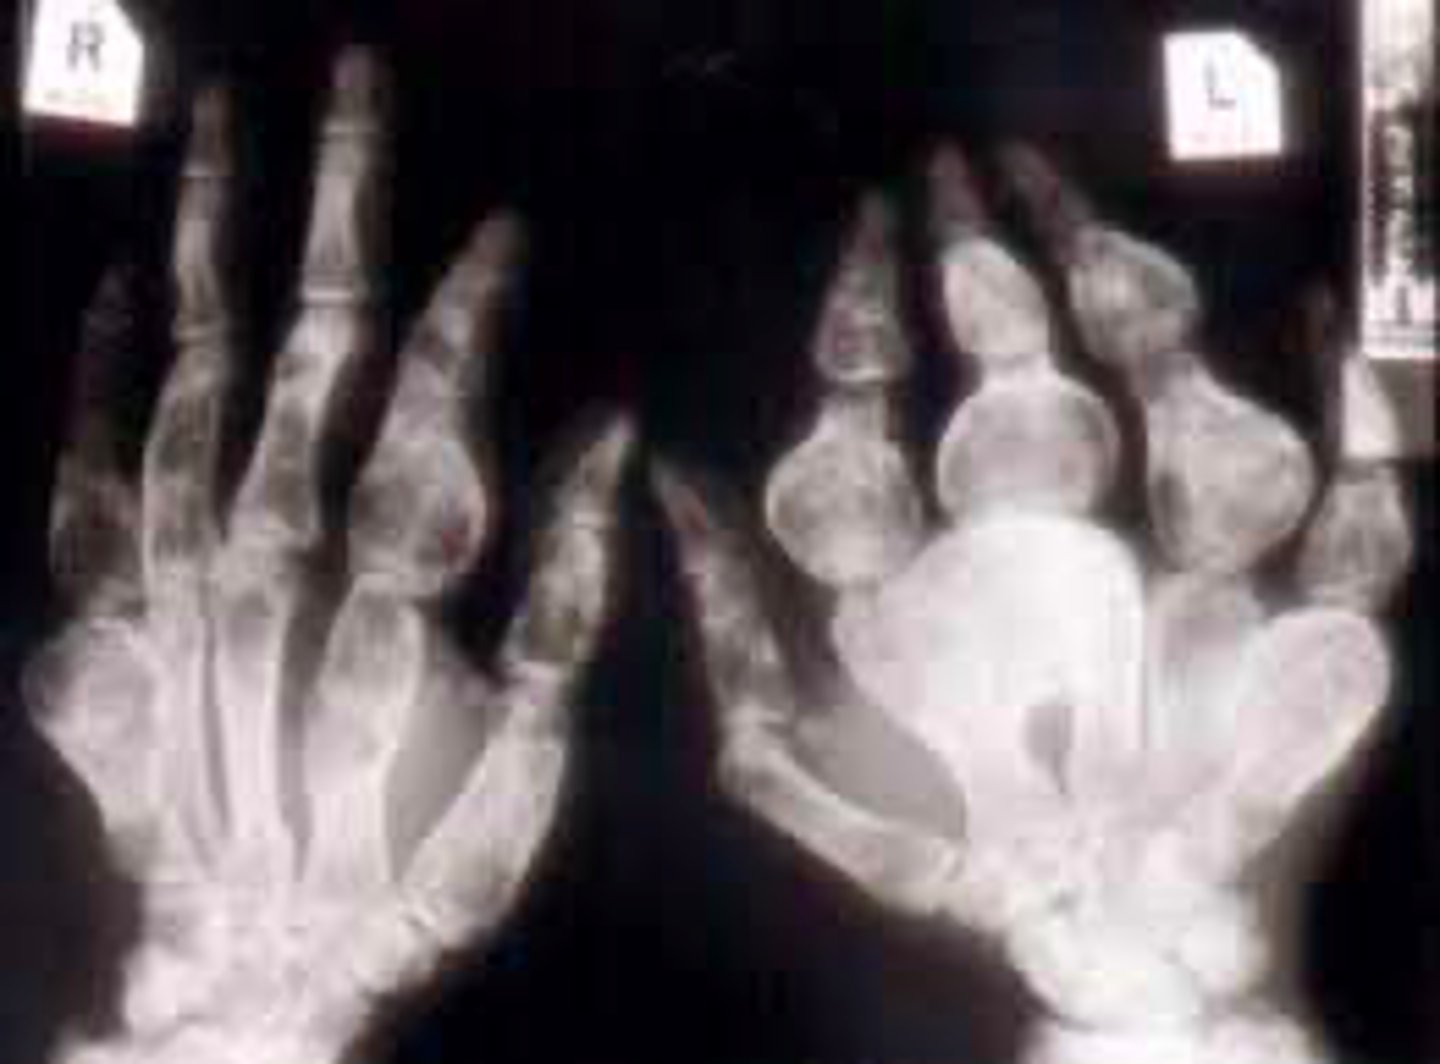

Vignette # 10

Sex: Male

Age: 24

Chief Complaint: Mechanic presents with loss of grip strength. The patient reported having swollen fingers that previous hurt but the pain went away.

Objective Findings: ROM in his hands are decreased, notable swelling of the tissue in his fingers

Diagnostic imaging: X-ray